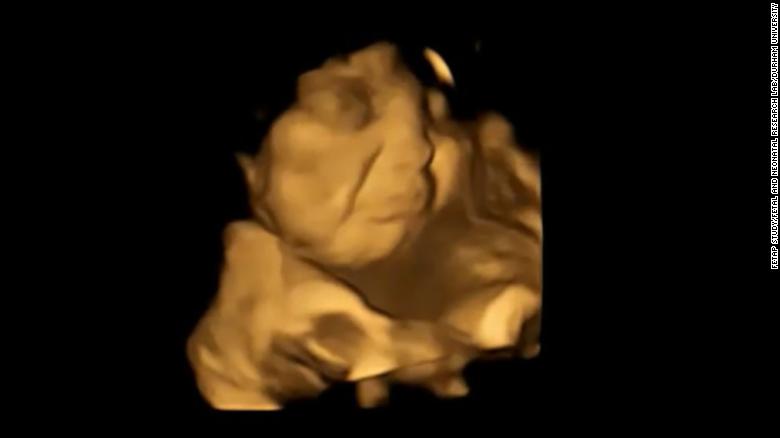

Τα έμβρυα παίρνουν πιο «γελαστό πρόσωπο» στη μήτρα όταν εκτίθενται στη γεύση των καρότων που καταναλώνει η μητέρα τους και «πιο θλιμμένη έκφραση» όταν εκτίθενται στη λαχανίδα (κέιλ), σύμφωνα με μελέτη που δημοσιεύθηκε στο περιοδικό Psychological Science.

Αφού περίμεναν 20 λεπτά μετά την κατανάλωση, οι γυναίκες υποβλήθηκαν σε 4D υπερηχογραφήματα, τα οποία συγκρίθηκαν με 2D εικόνες των εμβρύων.

Το τράβηγμα της γωνίας των χειλιών, που υποδηλώνει χαμόγελο ή γέλιο, ήταν σημαντικά υψηλότερο στην ομάδα του καρότου σε σύγκριση με την ομάδα της λαχανίδας και την ομάδα ελέγχου. Ενώ κινήσεις όπως η ανύψωση του άνω χείλους, η ρίψη του κάτω χείλους προς τα κάτω, το πάτημα των χειλιών και ένας συνδυασμός αυτών – που υποδηλώνει ένα πρόσωπο που κλαίει – ήταν πολύ πιο συχνές στην ομάδα της λαχανίδας σε σχέση με τις άλλες ομάδες.